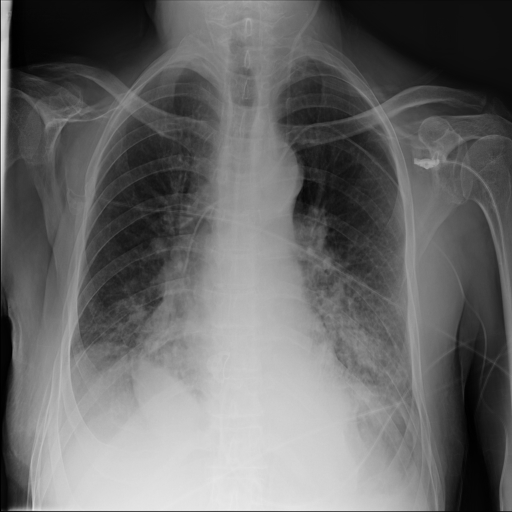

In Fig. 1, we show four ϵitalic-ϵ\epsilon-LDP-processed CXR images of clinical cases obtained with the image domain LDP, which directly imposes the Laplace mechanism on the input image, with different privacy budgets together with the original images. Fig. 2 shows four ϵitalic-ϵ\epsilon-LDP-processed CXR images of clinical cases obtained with DP-GLOW and different privacy budgets together with the original images. In case 1 for DP-GLOW, there is decreased permeability in the bilateral hilar regions. Although this hilar opacity tends to be preserved with a larger privacy budget, the entire image is degraded when the privacy budget becomes 101HWsuperscript101𝐻𝑊10^{1}\cdot H\cdot W. A similar tendency is observed in the images of all the four cases for DP-GLOW; for example, in case 4 with ϵ=101HWitalic-ϵsuperscript101𝐻𝑊\epsilon=10^{1}\cdot H\cdot W, the lung opacity suggesting pneumonia in the right lower lung field is well preserved, while the entire image is degraded.

Refer to caption

(a) Original

case 1

(b) ϵ=103HWitalic-ϵsuperscript103𝐻𝑊\epsilon=10^{3}\cdot H\cdot W

(c) ϵ=102HWitalic-ϵsuperscript102𝐻𝑊\epsilon=10^{2}\cdot H\cdot W

(d) ϵ=101HWitalic-ϵsuperscript101𝐻𝑊\epsilon=10^{1}\cdot H\cdot W

Figure 2: ϵitalic-ϵ\epsilon-LDP-processed CXR images obtained with DP-GLOW.